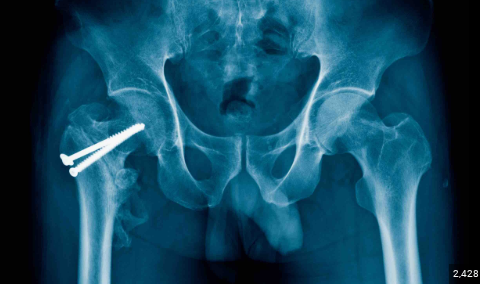

>>526325573

They drill a metal rod through your old gay bones. If you blur your vision and stare at picrel you can almost see Piers.

>If you blur your vision and stare at picrel you can almost see Piers.

I see hitler